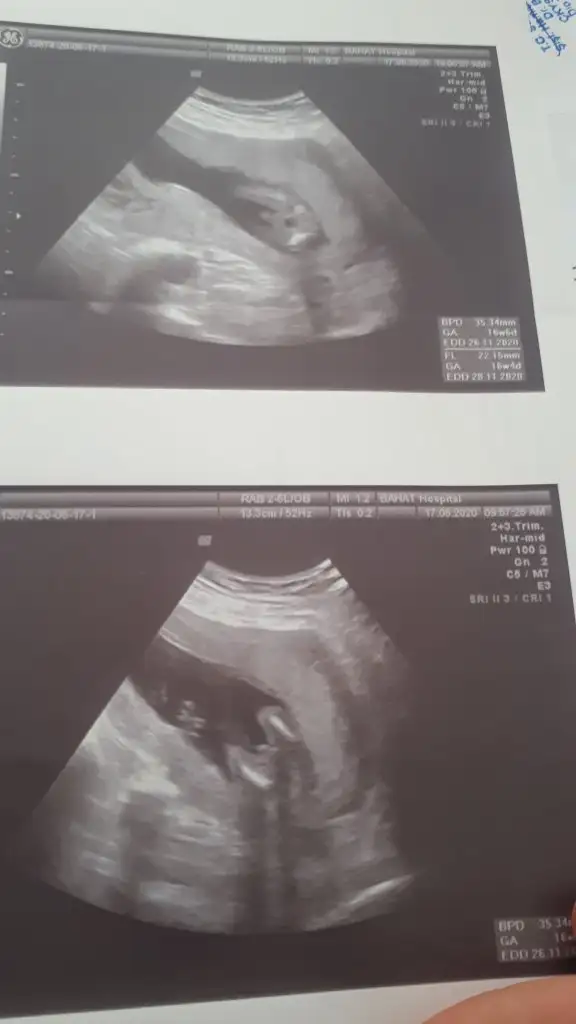

Ögrendinizmi kız tahmin etmiştimBenim bebeğimin cinsiyeti için de tahminde bulunur musunuz acaba. 16. Haftaya daha coook var

Üçlü taramada büyük ihtimalle kız olduğu söylendiNet degil usg tek tek çekermisiniz usgler yada başka usg olursa paylaşın 12-13 haftalarda olabilir şimdilik eminde değilim kız gibi gibi emin değilim tekrar usg paylaşın

Tahminim dogru saglıkla gelsinÜçlü taramada büyük ihtimalle kız olduğu söylendi